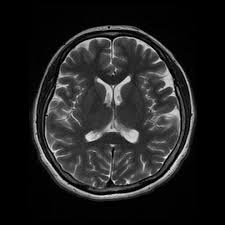

Meniere S Disease Symptoms And Causes Mayo Clinic from www.mayoclinic.org Get the facts in this comprehensive overview. Magnetic resonance imaging of the left inner ear of a me´nie`re's patient. This is the most common type of tinnitus. Tinnitus may be described as buzzing, ringing, roaring, whistling, or hissing and is sometimes variable and complex. It can be caused by ear problems in your outer, middle or inner ear. Discover 8 key ways to beat tinnitus naturally. Depending on the suspected cause of your tinnitus, you may need imaging tests such as ct or mri scans. The most common cause of tinnitus is damage and loss of the tiny sensory hair cells in the cochlea of the inner ear.

One of the most common causes of tinnitus is due to inflammation and poor circulation within the inner ear. As such, the symptoms and treatment options vary by person. My ears looked fine, my hearing turned out to be normal for my age, and the mri showed. Magnetic resonance imaging of the left inner ear of a me´nie`re's patient. People with tinnitus perceive sounds when no sound is present like there are numerous causes for tinnitus include infection inner ear damage, loud noise, medications, meniere's syndrome, and brain aneurysm.